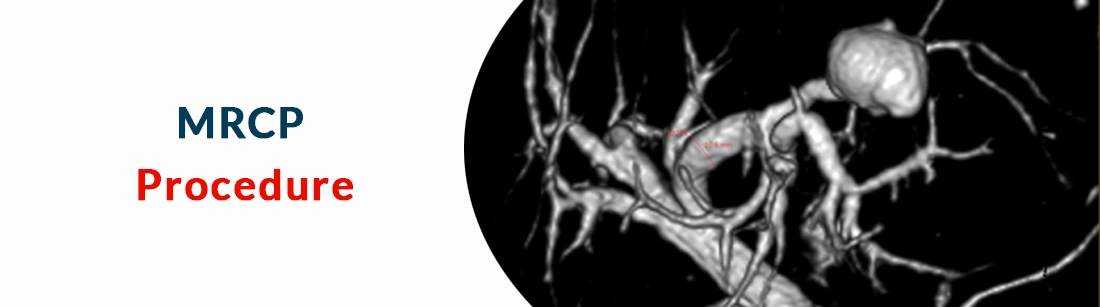

Magnetic Resonance cholangiopancreatography is one of the most important diagnostic tools used widely to obtain detailed 3D images of the abdomen as we as the region of hepatobiliary and pancreatic duct to diagnose various conditions associated with it this test proves to be an excellent technique to check for the different conditions related with the abdominal region in a very early phase.

MRCP test is a non-invasive technique and one of the most widely diagnostic tools used to create detailed 3d images of the abdominal region of the body it is a non-invasive process that uses radiowaves and requires a computer screen to evaluate and diagnose the condition to provide immediate and fast treatment of the condition detected.